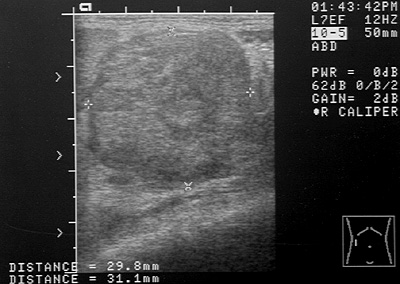

Ultrasound image of an abdominal mass

Figure 3: Ultrasound image of an abdominal mass